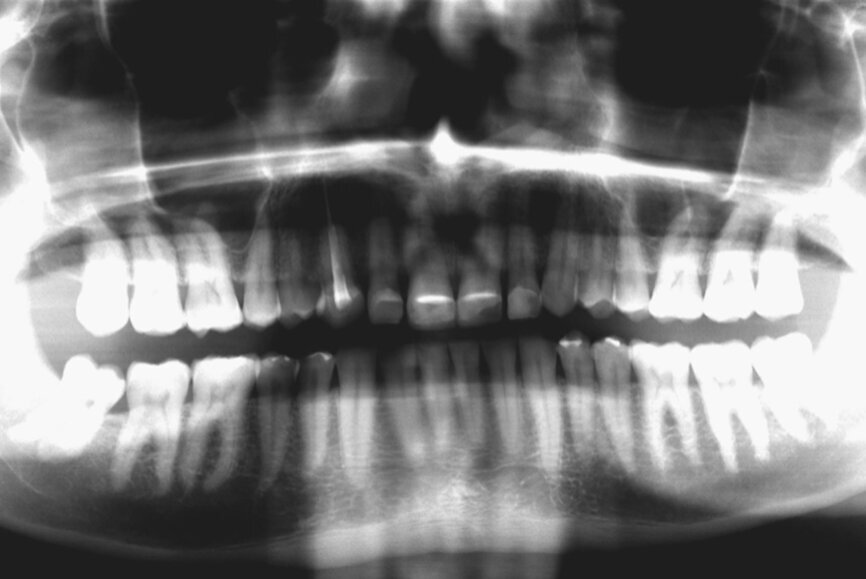

In 2015, a 47-year-old male patient presented complaining of pain in the TMJ. He also had an aesthetic request, since part of the veneer on one of the maxillary central incisors had broken off (Figs. 1–3). The clinical and radiographic analysis (Fig. 4) indicated a loss of bite height and tooth substance due to bruxism.

Fig. 4: Initial situation, panoramic radiograph (2015).